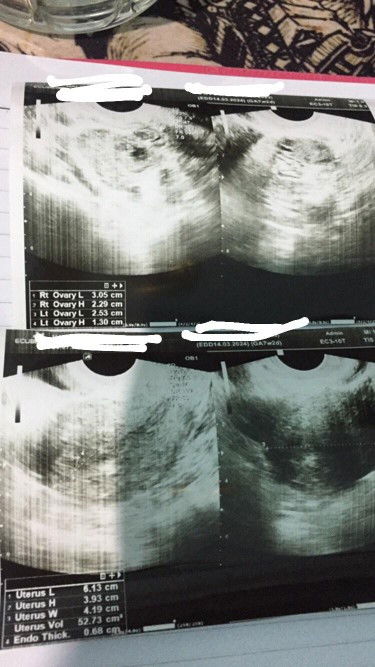

Bun aku baru dpt tespeck garis 2 terang hari ini dan aku langsung USG tp kata dokter masih penebalan dinding rahim, aku usg tv. Itu wajar ga ya Bu. ? 2 Minggu lagi aku disuruh balik. Kalo dr hitungan hpht aku udh 7w2d, cuma aku bilang ke dokter kalo haid ku ga teratur tanggal nya tp setiap bulan haid. Terus dokter bilang kalo nanti udh ada kantung nya ikutin yg di USG aja jadi ga ikut yang hpht#seriusnanya #bantusharing